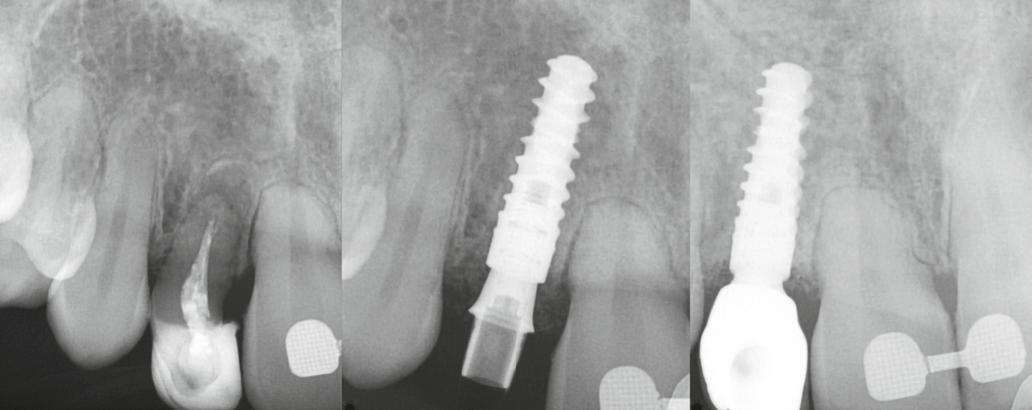

1. a–d. ábra: Műtét előtti állapot mind a négy páciensnél. 1. eset (a). 2. eset (b). 3. eset (c). 4. eset (d).

digitális implantátumtervezés követett (SICAT és Sidexis, mindkettő Dentsply Sirona; 1. ábra).

A sebészeti eljárás

Mind a hat implantátum esetén kétlépcsős műtétet végeztünk. Minden sebészeti eljárást bódítás, illetve preoperatív szisztémás antibiotikus terápia nélkül végeztünk. A négy eset közül kettőnél leukocitában és vérlemezkében gazdag fibrint (L-PRF) alkalmaztunk a beavatkozás során (IntraSpin, BioHorizons; 2. táblázat). Minden esetben a pontos CERALOG menetvágási (maximum 15 ford./perc) és fúrási (maximális fúrási fordulatszám: 550–800 ford./perc) protokollt követtük. Az összes implantátumot manuálisan helyeztük be 35 Ncm maximális nyomatékkal. Az implantátumokba PEEK zárócsavar került (2. ábra). A lágyszövetet atraumatikus, felszívódó varrattal, szorosan zártuk/összevarrtuk. A műtétek után szövődmények nem jelentkeztek. A pácienseket arra kértük, hogy a műtét utáni héten naponta kétszer öblögessenek klórhexidinnel (PERIO-AID, 0,05%, DENTAID). Az alsó állcsontnál három hónapos, a felső állcsontnál öt hónapos gyógyulási időt vettünk figyelembe. Három hónap (1. eset) és öt hónap (2., 3. és 4. eset) elteltével a műtétek második stádiumát helyi érzéstelenítés mellett végeztük. A gyógyu-

lási csavarokat (PEEK titáncsavarral) maximum 15 Ncm-rel húztuk meg (3–6. ábra). Az összes implantátum kiváló stabilitást mutatott (a mérésekhez Periotestet használtunk, a Medizintechnik Gulden jóvoltából), és teljesen osszeointegrálódott. Ezt a radiológiai vizsgálatok is megerősítették.

3. a–b ábra: Röntgenfelvételek három hónap után (a) és a gyógyulási csavarok behelyezve (b, 1. eset).

4. a–b ábra: Röntgenfelvételek öt hónappal később (a) és a gyógyulási csavarok behelyezve (b, 2. eset).

5. a–c ábra: Röntgenfelvételek öt hónappal később (a) és a gyógyulási csavarok behelyezve (b és c, 3. eset).

6. a–b ábra: Röntgenfelvételek öt hónappal később (a) és a gyógyulási csavarok behelyezve (b, 4. eset).